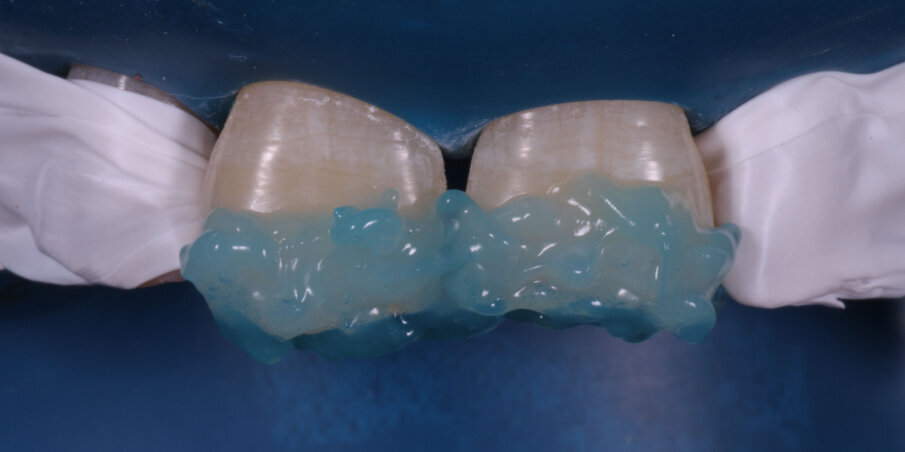

Enamel Shade A3 of a nanocomposite (FiltekZ350XT,3M) was adapted on the previously scored putty index, placed in position and light-cured for 20 seconds. This gave us the palatal shell on which we layered the Dentin and Body Shades (A3) sequentially (Fig 10 -12). Proximal walls were created with enamel shade composite and thin mylar strips with a palatal pull-through technique. A thin final layer of enamel shade was applied and photocured (Fig 13-14).

Fig 14: Photocuring with glycerin gel barrier